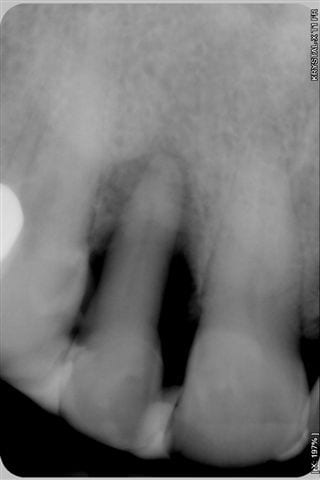

cas d'un patient arrivé vendredi en urgence, volumineux abcès vestibulaire sans fistulisation, au sondage poche de 8 mm en proximal: mésiale et distale, gencive attachée en vestibulaire,mobilité 3 pas le temps de prendre des photos, mais simplement une radio.

patient revu le 25 aout pour biostimulation, 4ème radio prise lors de la séance montre un début de régénération osseuse.

La 5ème radio prise ce jour avec biostimulation en post op, montre que la régénération, que beaucoup d'entre vous pensait impossible, est bien entrain de se faire.

et voilà le résultat en radio lors des recalls du patient pour biostimulation:

patient revu le 25 aout pour biostimulation,2ème radio prise lors de la séance et qui montre un début de régénération osseuse.

La 3ème radio prise ce jour avec biostimulation en post op, montre que la régénération, que beaucoup d'entre vous pensait impossible, est bien entrain de se faire.

1-Le temps entre 1ere et 3e radio

2-Les radio ne semblent pas très standardisées au niveau des contrastes. La 1ere est très foncée, donc le défaut osseux peut sembler plus grave et la 3e est pâle, ce qui montre plus d'os. Ou bien je me trompe...

Net différentiel de contraste et/ou exposition entre la 3ème et les deux premières, non?

première radio le 22/07 et la 3ème aujourd'hui

Je me demandais ce qui pourrait encore vous faire douter, bingo "la première radio est plus sombre que la 3ème" eh bien en voici une prise le 22/7 en urgence et moins sombre, aurez vous encore des doutes quant au bien fondé d'un traitement conservateur laser assisté???